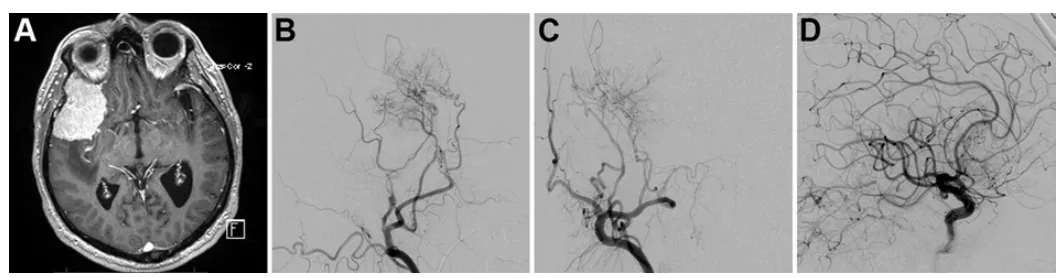

诺亚术前影像,左侧岩斜区脑膜瘤,呈不均匀强化。

MRI诺亚术前栓塞后3D-CISS序列多平面重建MRI,可见脑膜瘤与神经血管结构的复杂关系。

由于已知该肿瘤的血供丰富,福教授在手术前进行了DSA检查,显示其供血动脉主要为咽升动脉及脑膜垂体干。为降低后组颅神经损伤风险,选用弹簧圈栓塞。栓塞可减少出血、软化肿瘤,便于切除。

诺亚术前栓塞咽升动脉及脑膜垂体干

矢状位MRI显示肿瘤经栓塞后血供部分阻断(部分去血管化)